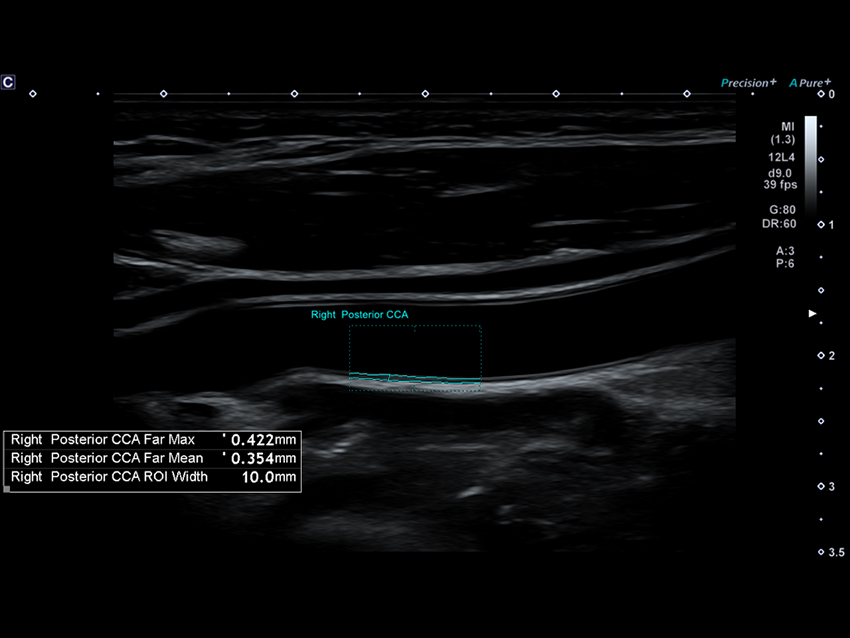

Aplio beyond tích hợp các công cụ AI thông minh hỗ trợ nhận diện cấu trúc giải phẫu, tự động đo lường và phân tích, giúp rút ngắn thời gian thực hiện thủ thuật, nâng cao độ nhất quán và tin cậy kết quả cho bác sĩ. Các thuật toán tự động giúp xác định vị trí cấu trúc, hỗ trợ trong các ứng dụng phức tạp và nâng cao hiệu quả quy trình làm việc.